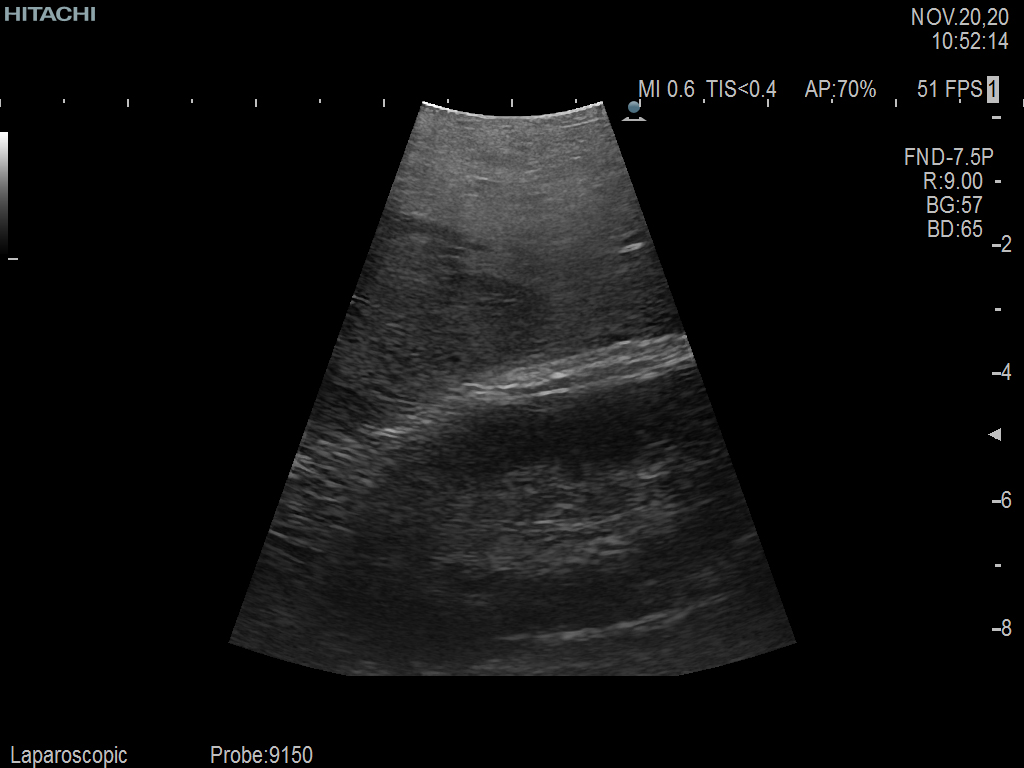

Curved array deep penetration “I” style finger-grip transducer for open kidney surgical procedures. Allows for palpating organs and scanning at the same time.